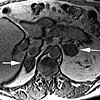

МРТ надпочечников ребенку показана для выяснения причин нарушения работы парных эндокринных желез, расположенных в области верхних полюсов почек. Посредством магнитно-резонансной томографии выявляются, главным образом, опухоли коркового слоя (аденомы, альдостеромы, кортикостромы, андостеромы) и мозгового слоя (нейробластомы, феохромоцитомы), а также гиперплазия коры надпочечников. С целью более точной топической и дифференциальной диагностики используется контрастное усиление. В детской эндокринологии проведению МРТ надпочечников предшествует гормональное обследование и УЗИ желез.